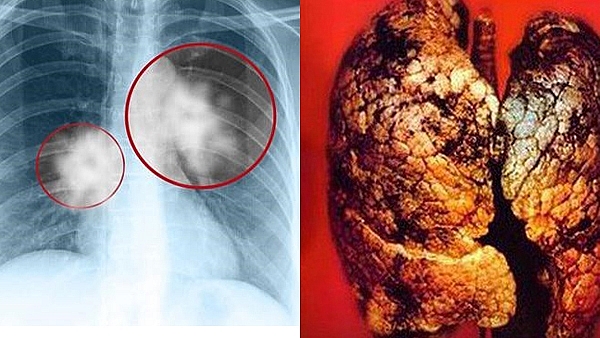

Điều trị ung thư phổi - Ảnh 1.

• Xét nghiệm hình ảnh: Bao gồm X-quang ngực, siêu âm, máy tính cắt lớp (CT), hình ảnh từ phổ đồng tử (PET-CT) và hình ảnh từ từ tính (MRI).